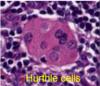

parathyroid

Oxyphil cell.